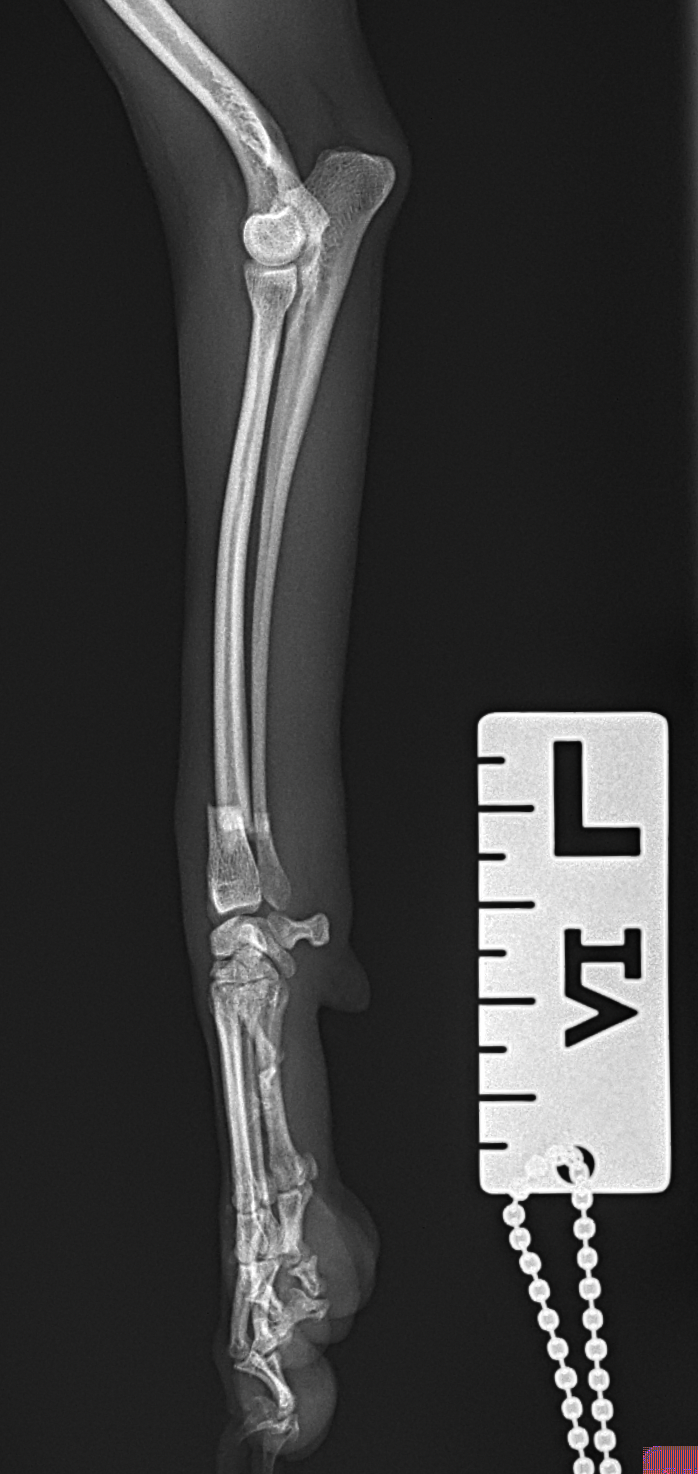

橈骨固定術 #270 極小犬(1.4kg)の橈骨固定術依頼です。骨幅3.8mmに対して1.2 Titanium Locking Plateと自家海綿骨移植を実施しています。初期固定強度を担保するために、外固定を併用しながらしばらくは安静が必要です。 症例カテゴリー 放射線治療整形外科軟部組織外科脳神経外科内科腫瘍外科救急・集中治療リハビリテーション科腫瘍内科内視鏡科脳神経科呼吸器外科中医・漢方猫の腎移植循環器科